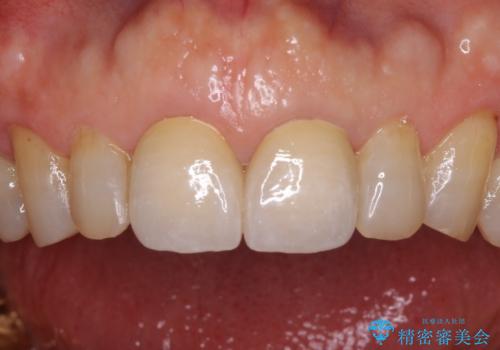

前歯の隙間をオールセラミッククラウンで自然に

折角なのできれいに仕上げたいとのことで、オーダーメイドタイプのクラウンを選択されました。色調を周りのご自身の歯と合わせることができるため、自然な仕上がりをご希望の方におすすめです。